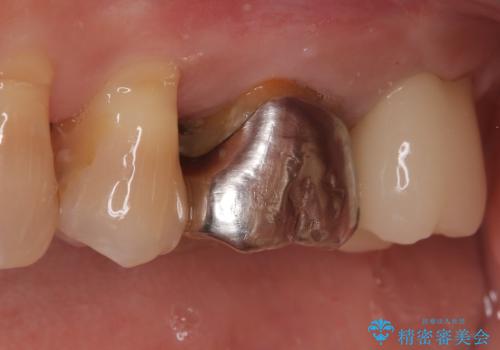

【根管治療】ズーンと痛い歯の治療。

- 奥歯付近がジーンと痛いことを主訴に来院されました。

左上7番の歯は、歯髄検査にて反応を示し、歯周ポケットはありませんでした。

親知らず抜歯を行い、痛みの変化や歯根吸収の有無を確認したのち、抜髄処置を行っています。

症状改善し、遠心の骨の回復も認めます。

バイオセラミックシーラーを使用して根管充填を行っています。